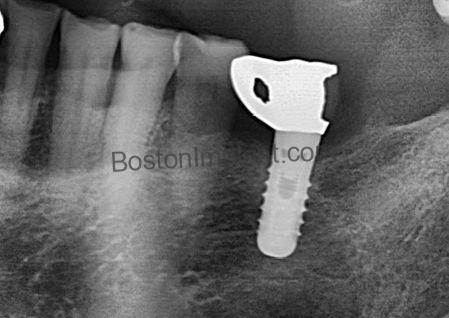

(4) Implant Fracture

While dental implants are strong, they can sometimes fracture, or their internal components (like abutment screws) can strip. Most dental implants placed today are internal connection implants, which are generally reliable when the implant diameter is sufficient and the placement is correct. However, their inherent design can result in a thinner top collar area, making them potentially susceptible to fracture or stripping.

HOW TO FIX THIS: To mitigate these risks, I prioritize placing implants with sufficient wall thickness. I also prefer tissue-level implants; their naturally thicker collar provides superior resistance to fractures.